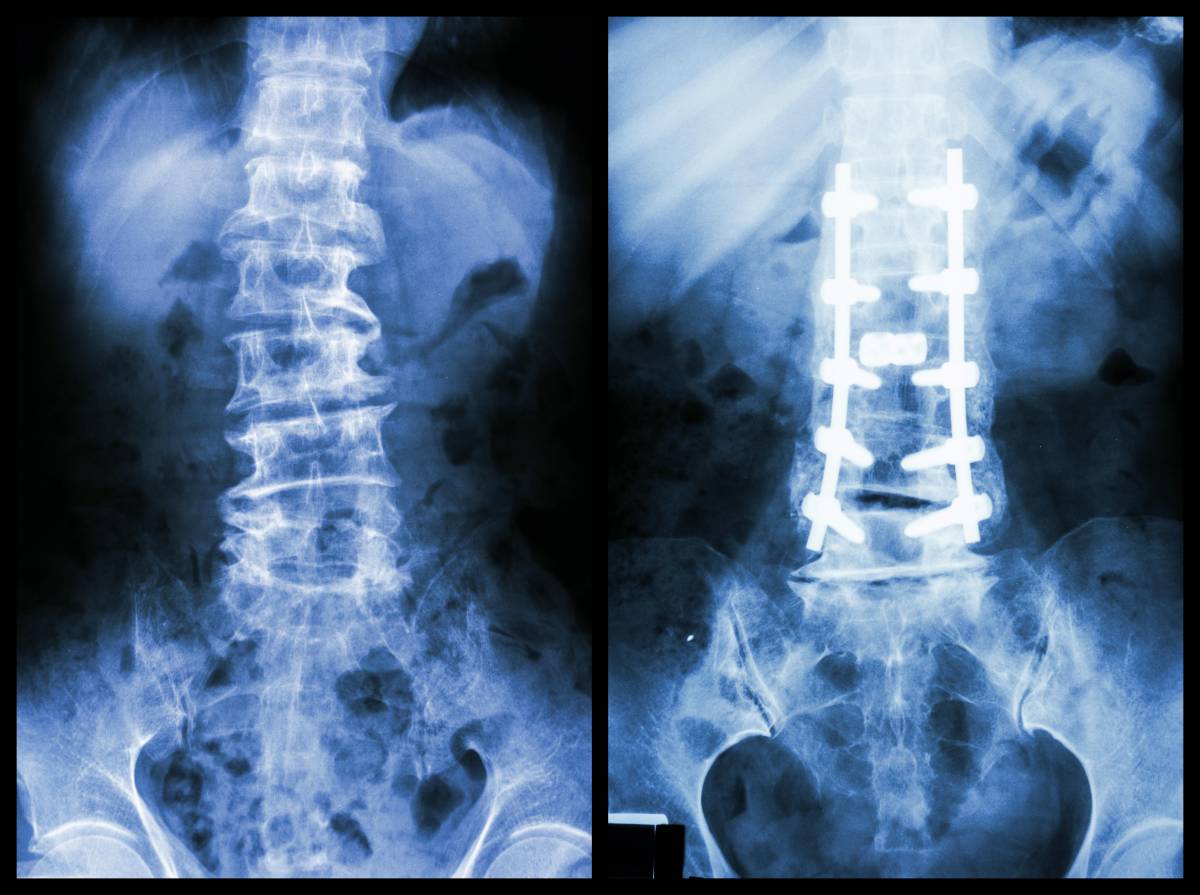

自1934年美国哈佛大学医学院首次用手术治愈腰椎间盘突出症算起,腰椎间盘突出症的手术治疗史已达80多年,手术方式也不断更新,如微创经皮椎间孔镜技术、腰椎后路减压椎间融合术、人工腰椎间盘置换术等,技术逐步完善,治疗更加精准,但术后仍会出现切口愈合不良、感染、神经损伤等并发症,严重影响患者的康复效果。所以,术后护理不容忽视,患者更是要注意坚持腰背肌锻炼,如此才能减少并发症,加速康复,避免复发。具体应做到——

术后1个月、3个月、6个月、12个月定期门诊复查。1年以后如果没有问题,之后复查为每年1次,再之后可延长为3年1次。复查内容主要是拍X光片,看手术部的愈合情况,以及内固定物情况。